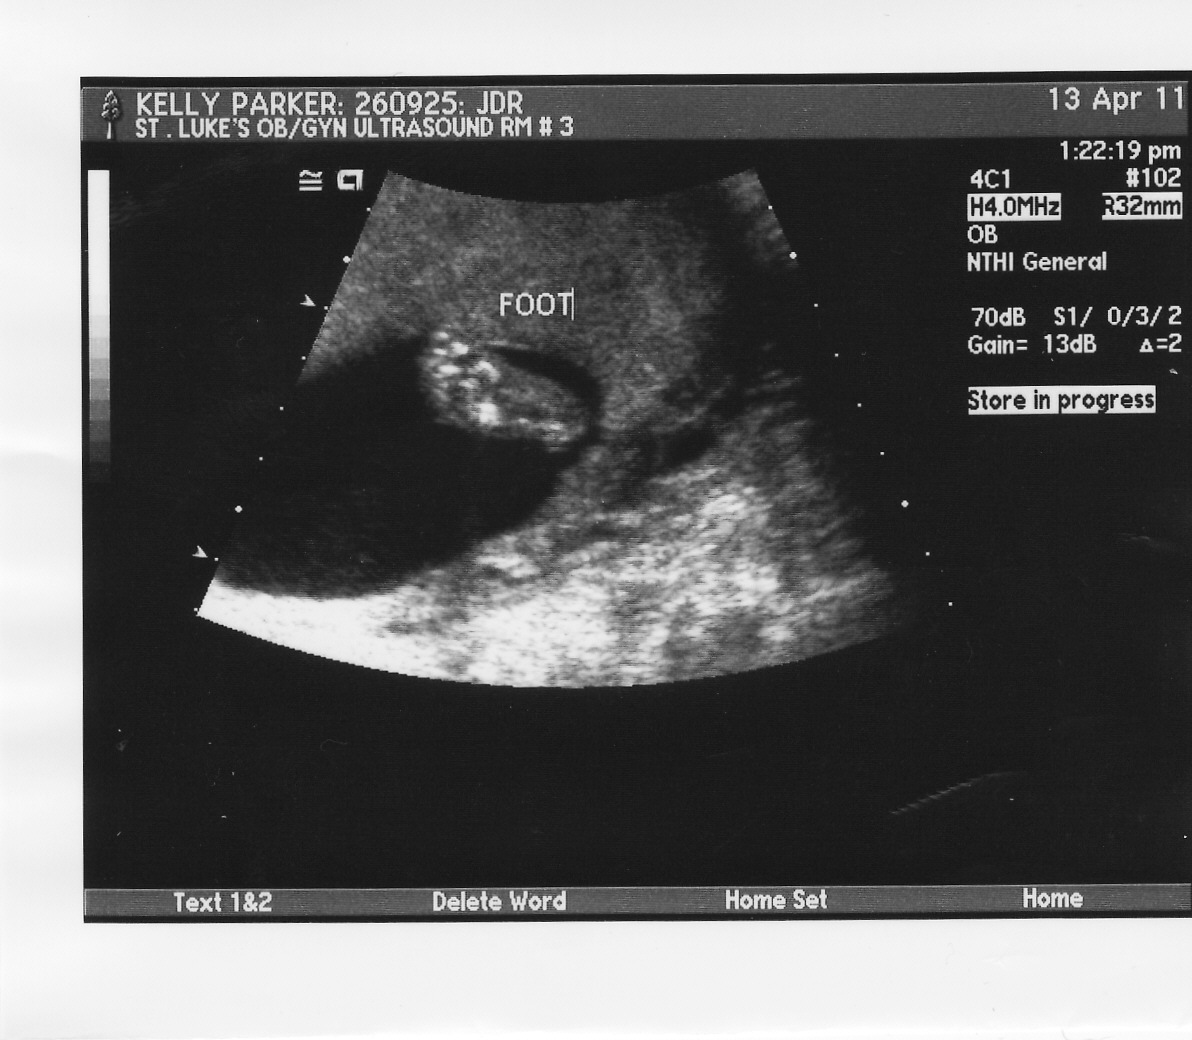

Here is a picture of a tiny little foot! Isn't it cute?!?!